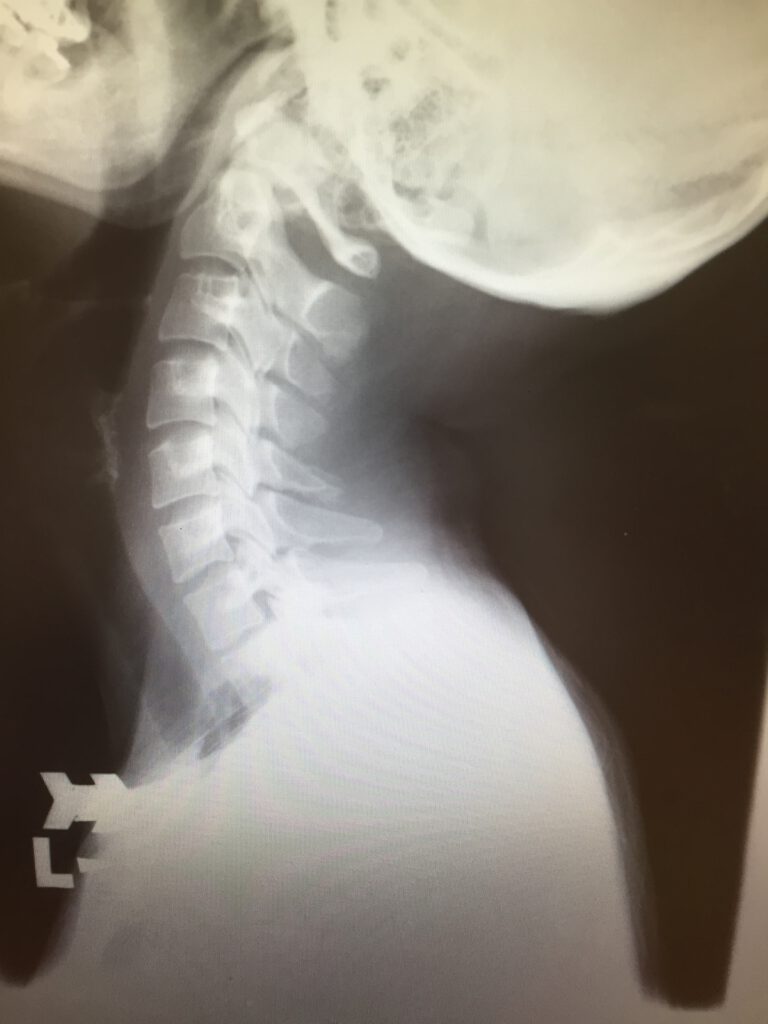

レントゲンやエコー検査を用いて、骨・関節・筋肉の状態を詳しく調べます。症状が軽い場合でも、まずは骨折や神経障害といった重い異常がないか確認することが大切です。

まず問診を行い、必要に応じてレントゲンやエコー検査を実施します。診断内容に基づき、以下の対応を行います。

- 精密検査(MRIなど)の紹介状作成